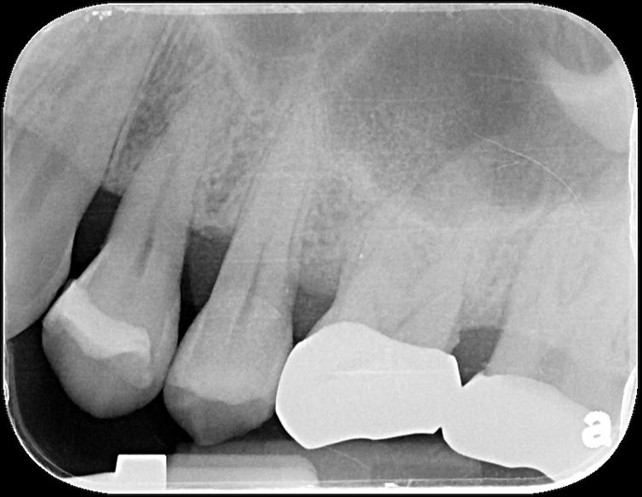

治療後口內照

全鋯冠密合度良好

術前、術後比較